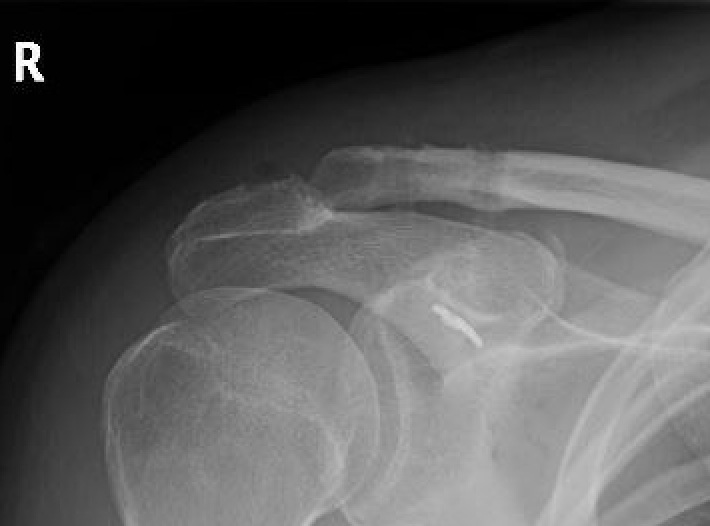

III AC & CC ligaments ruptured (displaced up to 100% of CC distance)

V High dislocation (100 - 300% CC distance) - disrupted trapezius & deltoid and end of clavicle subcutaneous

VI Subcoracoid dislocation

X-rays

Zanca view

- specific for AC joint

- 10o cephalad, 50% underpowered

Stress views

- hold weights in each arm

Normal

- 50% of population overriding clavicle

- 2% under riding

- 29% incongruent

- joint width 0.5-7 mm